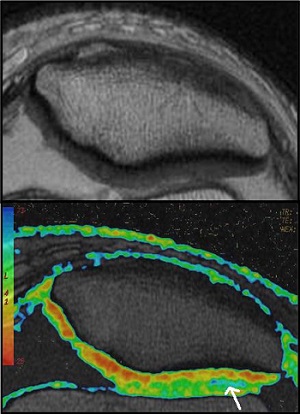

T2 Map cartigram

T2 MAP is used to noninvasively detect changes in the collagen component of the extracellular matrix of cartilage. T2 MAP acquires multiple scans at each location; each set of scans has a unique TE resulting in a set of gray scale images that represent different T2 weighting.

The acquired data can be processed in READY View to produce T2 color maps, which demonstrate more subtle changes in cartilage ultrastructure that are not visible on gray scale MR images. The T2 map and the parametric images produce visible image contrast changes in early stages of cartilage degeneration such as osteoarthritis.

The collagen in the radial zone of articular cartilage, close to the subchondral bone is highly ordered, with only small quantities of mobile water. By contrast, the collagen in the transitional zone is more randomly oriented, with increased mobile water and more prolonged T2 values. Increased T2 relaxation times within cartilage have been associated with matrix damage, particularly loss of the orientation of the collagen matrix.